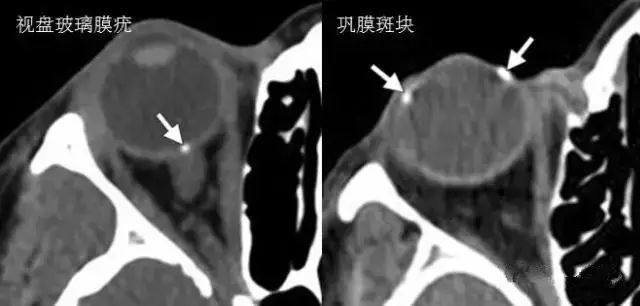

鉴别诊断:

【眼球|诊断眼球外伤时,影像医生要留心的6点!】1.脉络膜小疣:视神经盘附近的通常是与黄斑变性有关

2.巩膜斑块:沿内直肌和外直肌附着点的钙化也称为巩膜斑块 , 常见于老年人 。

3.常见的用于治疗视网膜脱离的材料包括巩膜条带 , 硅油 , 以及气体 。